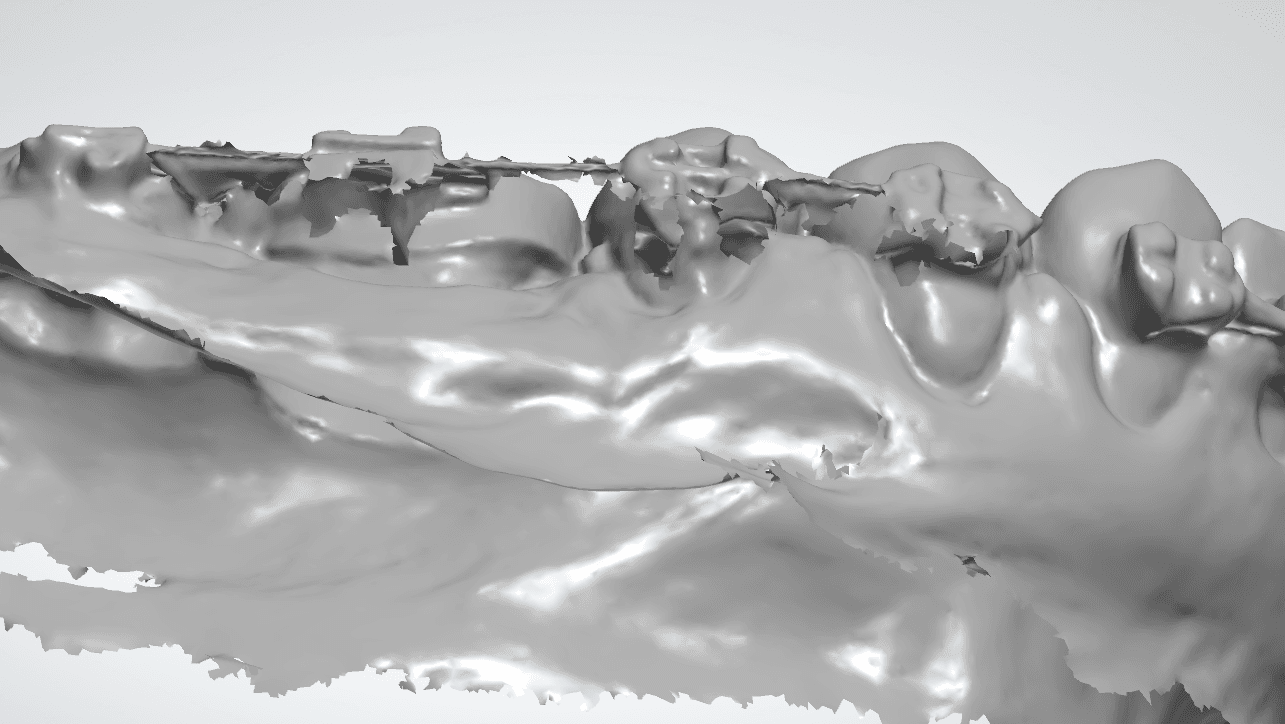

Falha de “Costura”

O escaner funciona tirando varias fotos da boca e vai “costurando” uma com a outra, formando uma imagem 3D, como se estivesse tecendo uma malha de tecido, tanto que é muito comum usar o termo “Malha” para se referir a um escaneamento 3D.

É muito comum você ter um defeito nessa junção da malha vestibular e lingual nas incisais Bateria Labial (tanto superior quanto inferior), esse defeito também conhecido como “falha de costura”.

Apesar de parecer um defeito pequeno ele pode prejudicar a adaptação do alinhador fatalmente por um lado da boca não ter alinhamento com o outro.